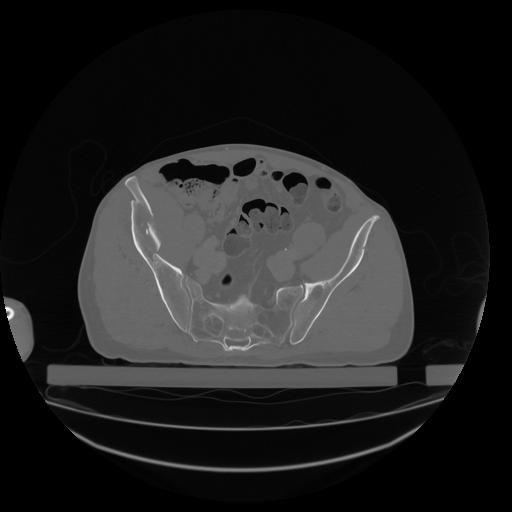

34 CUERPO,CE,Vol,1.0,CUERPO,,